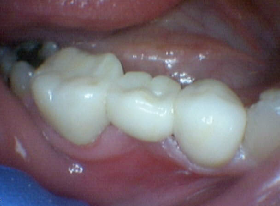

Zirconia Bruxir Crows, Cuspal Fracture